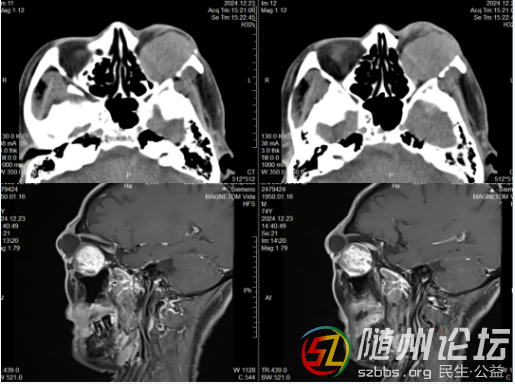

患者入住神經(jīng)外科后,神經(jīng)外科主任程勇、主管醫(yī)生李強及時組織全科進(jìn)行術(shù)前討論。經(jīng)顱腦CT和MRI影像提示,患者左側(cè)眶內(nèi)可見類圓形腫物,長T1長T2信號,大小約3.8×3.0cm,周圍下直肌、外直肌受壓向上移位,視神經(jīng)明顯受壓;由于眼眶空間有限,隨著腫瘤逐漸增大,眼球受到擠壓而突出,這不僅嚴(yán)重影響了患者容貌,還致使眼瞼外翻充血,反復(fù)引發(fā)結(jié)膜炎。更糟糕的是,腫瘤壓迫眶內(nèi)肌肉與視神經(jīng),使眼球運動受限,視力持續(xù)下降現(xiàn)幾乎完全喪失,必需盡快手術(shù)切除腫瘤才能緩解對視神經(jīng)的壓迫,挽救殘存的視力,恢復(fù)正常容貌。

顱腦CT和MRI檢查影像